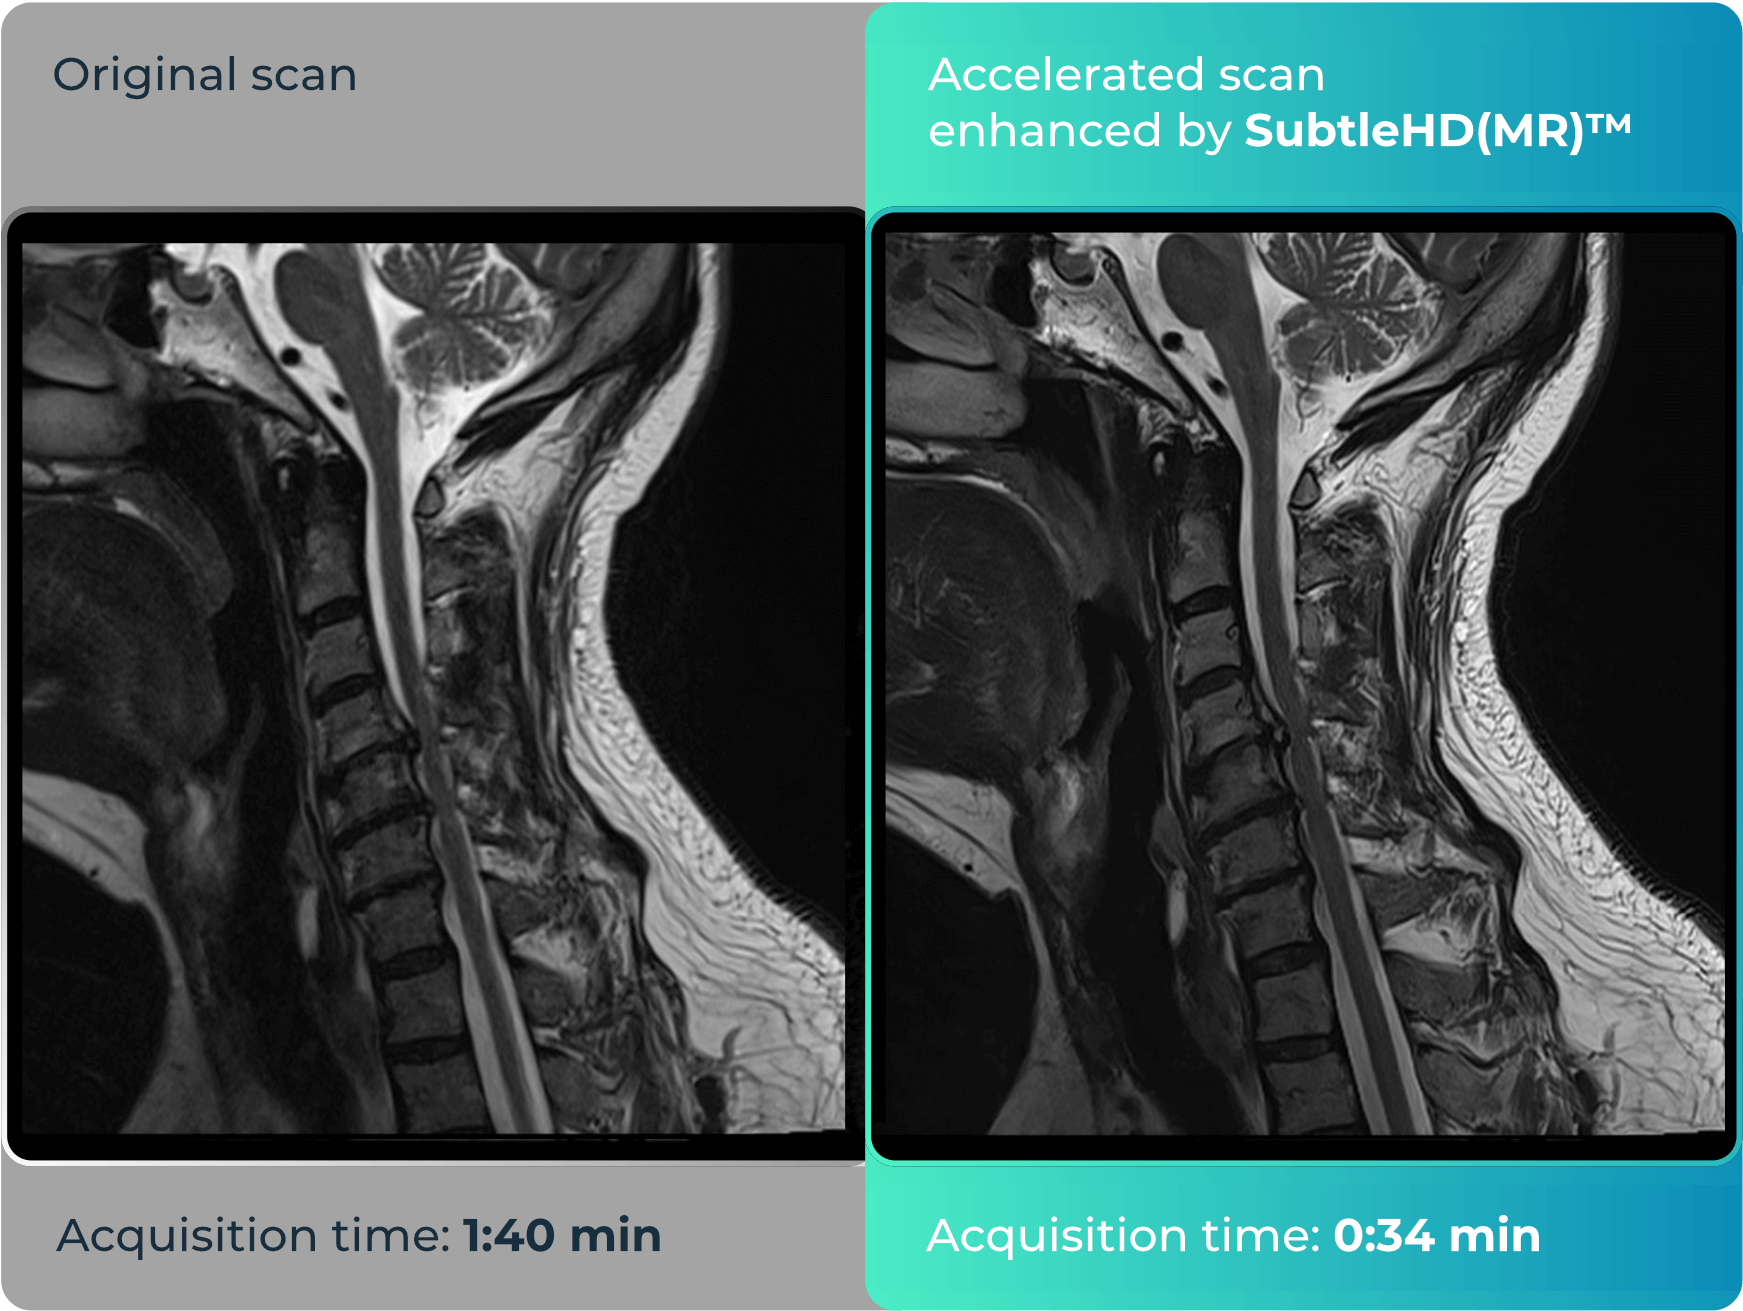

SubtleHD(MR)™

Uses denoising and increased sharpness to dramatically improve image quality on up to 80% faster MRI sequences.